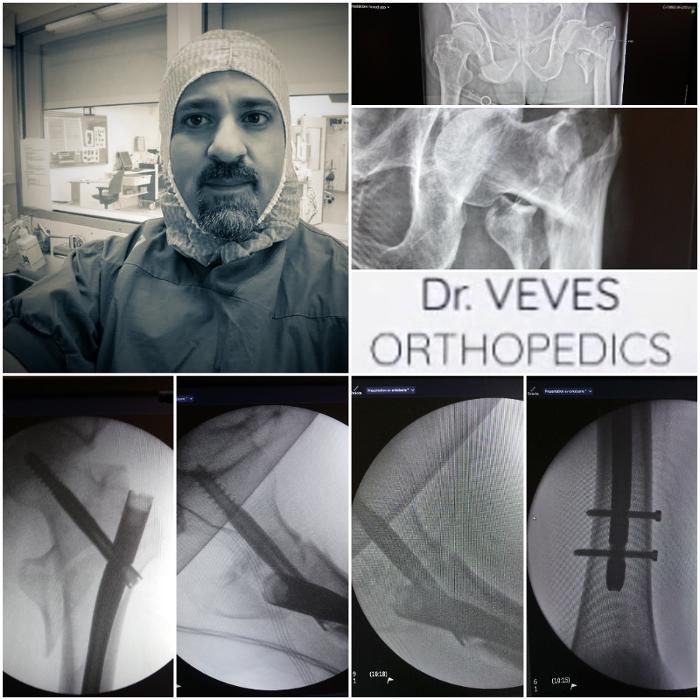

Ορθοπαιδικός Παγκράτι, θεραπεία αρθρίτιδας Παγκράτι, ρήξη μηνίσκου Παγκράτι

ρήξη χιαστού Παγκράτι, ορθοπαιδικό ιατρείο Παγκράτι, ορθοπαιδικός Παγκράτι

Ρήξη μηνίσκου Παγκράτι, ρήξη χιαστού Παγκράτι, ορθοπαιδικό ιατρείο Παγκράτι

Αρθροσκόπηση γόνατος Παγκράτι, Ορθοπαιδικός Παγκράτι, χειρουργός ορθοπαιδικός Παγκράτι, ορθοπαιδικοί ιατροί Παγκράτι, ορθοπαιδικό ιατρείο Παγκράτι

Ρήξη μηνίσκου Παγκράτι, ρήξη χιαστού Παγκράτι, ορθοπαιδικό ιατρείο Παγκράτι